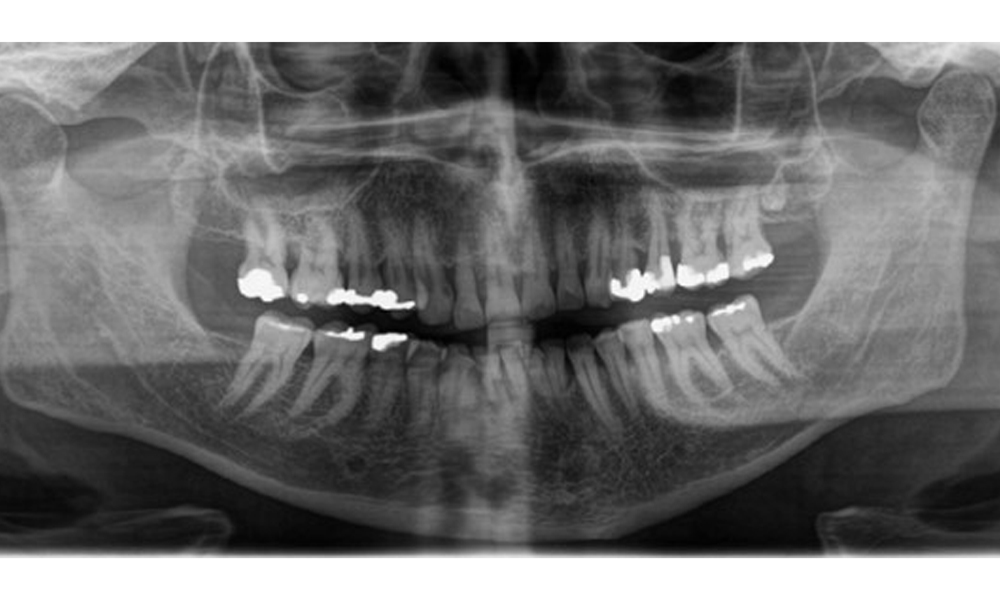

Se observă dentiție adultă completă, cu pierdere osoasă generalizată între 20-50% și zone multiple de pierdere osoasă verticală. Examenul radiologic nu a evidențiat carii vizibile. (Fig. 7)